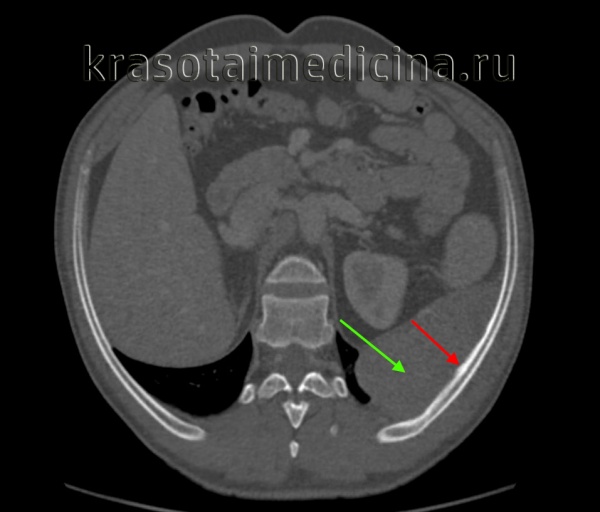

![КТ ОГК. Патоморфологически подтвержденная саркома Юинга 10-го ребра слева. Кортикальная пластинка ребра с внутренней стороны неравномерно утолщена (красная стрелка). Определяется массивное мягкотканное образование грудной стенки (зеленая стрелка).]()

КТ ОГК. Патоморфологически подтвержденная саркома Юинга 10-го ребра слева. Кортикальная пластинка ребра с внутренней стороны неравномерно утолщена (красная стрелка). Определяется массивное мягкотканное образование грудной стенки (зеленая стрелка).